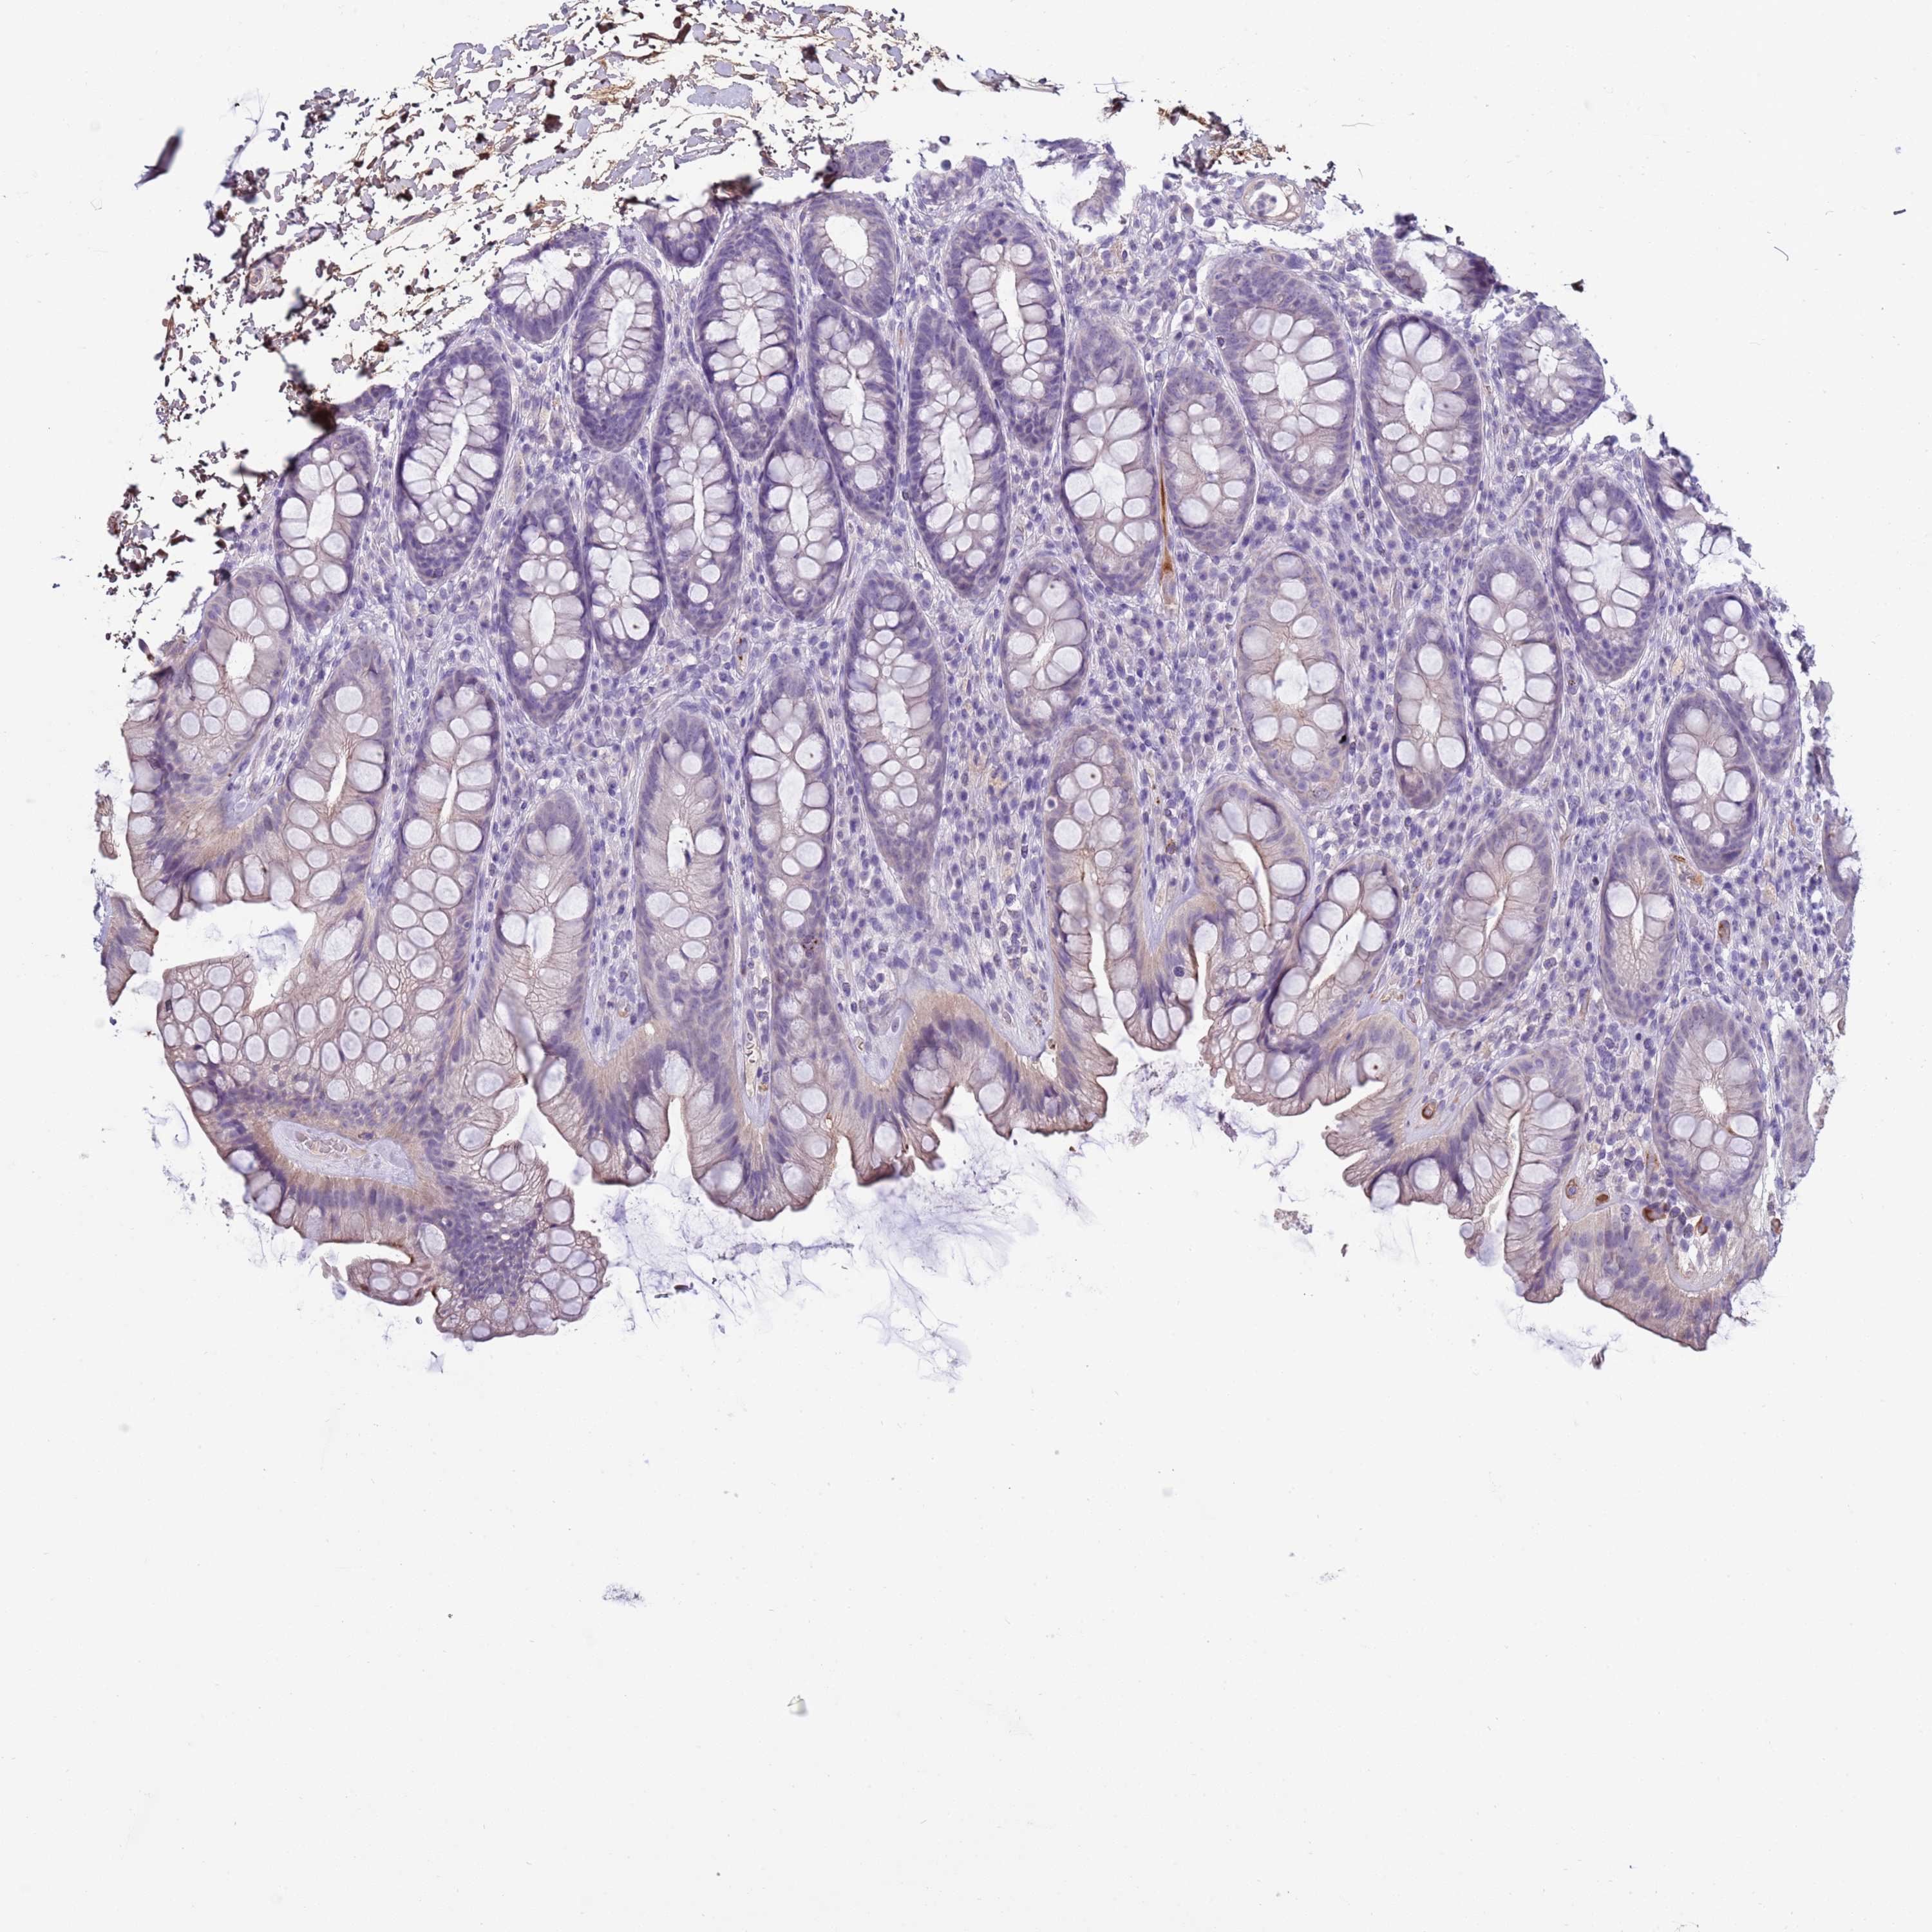

TRIM51